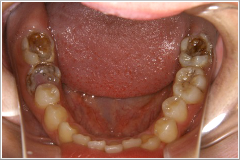

正月気分間覚めやらぬ1月8日、「前歯が折れてしまって、成人式に出られないんです。何とかならないでしょうか?」 という電話がありました。晴れの舞台に“歯っ欠け”ではさすがに気の毒で、「仮歯くらいなら、なんとかなりますよ」と答え、来院してもらうことになりました。その患者さんは20歳の女性(Cさん)で、左の写真の様なお口の状態でした。